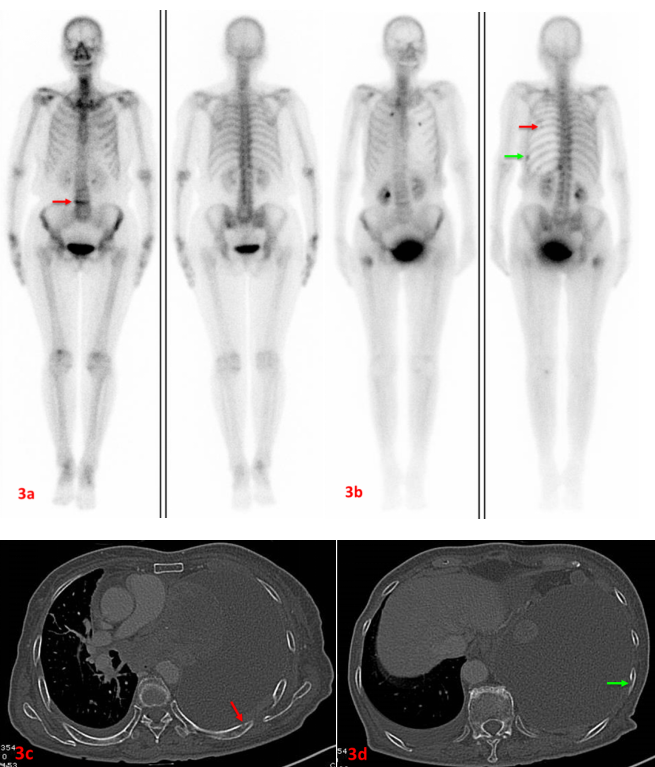

老年女性,左肺腺癌。初次ECT(3a圖)示L4(3a紅箭)代謝異常增強(qiáng),考慮壓縮性骨折。7個月后復(fù)查ECT(3b圖)示雙側(cè)多根肋骨、右側(cè)股骨上端代謝異常增強(qiáng),考慮多發(fā)骨轉(zhuǎn)移。L4代謝較前片明顯減低。同期CT檢查可見左側(cè)第7后肋(3c紅箭)、左側(cè)第9后肋(3d綠箭)溶骨性破壞。此病例證實了ECT定期復(fù)查的必要性,建議惡性腫瘤患者3-6個月復(fù)查一次。